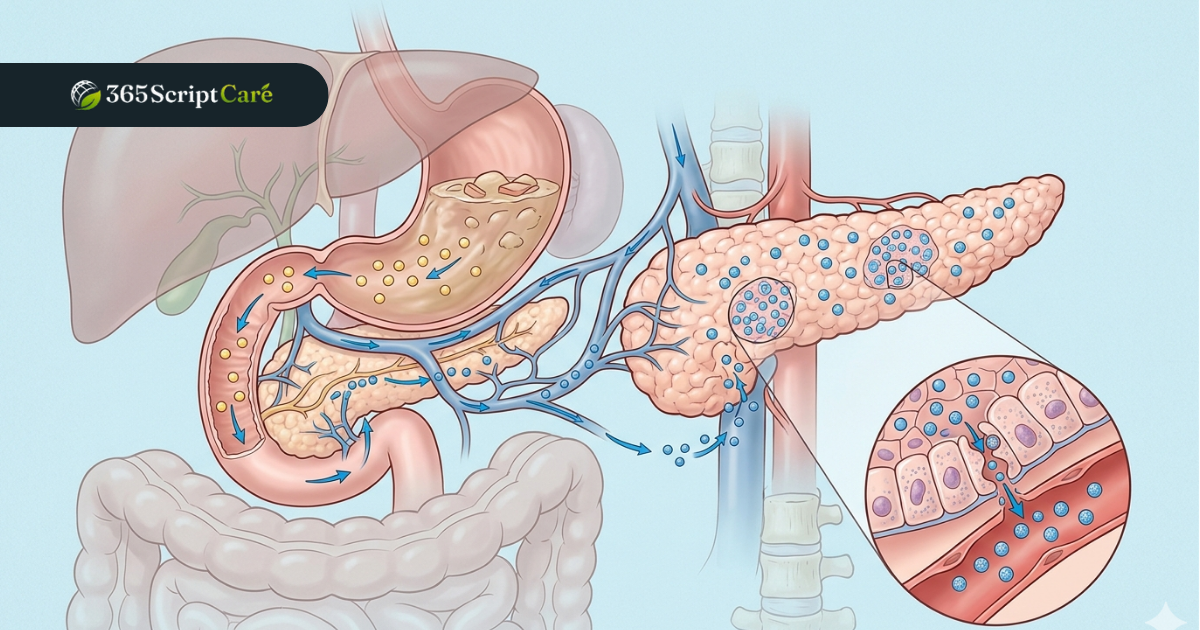

Once your body is familiar with Semaglutide, the 0.5 mg Ozempic dose kicks in as an active treatment level. At this stage, Ozempic stimulates GLP-1 receptors in the pancreas, prompting the release of insulin after meals. Digestion slows down, appetite decreases, and blood sugar levels start to stabilize. Many patients feel noticeably less hungry during the day at this Ozempic dose.

The 2 mg Ozempic dose is the strongest available. It is reserved for patients who have not met their treatment goals at 1 mg. At this level, Semaglutide delivers its most powerful effect on insulin production, gastric emptying speed, and hunger signaling. Patients taking the 2 mg Ozempic dose often see the most significant shifts in both blood sugar and body weight.